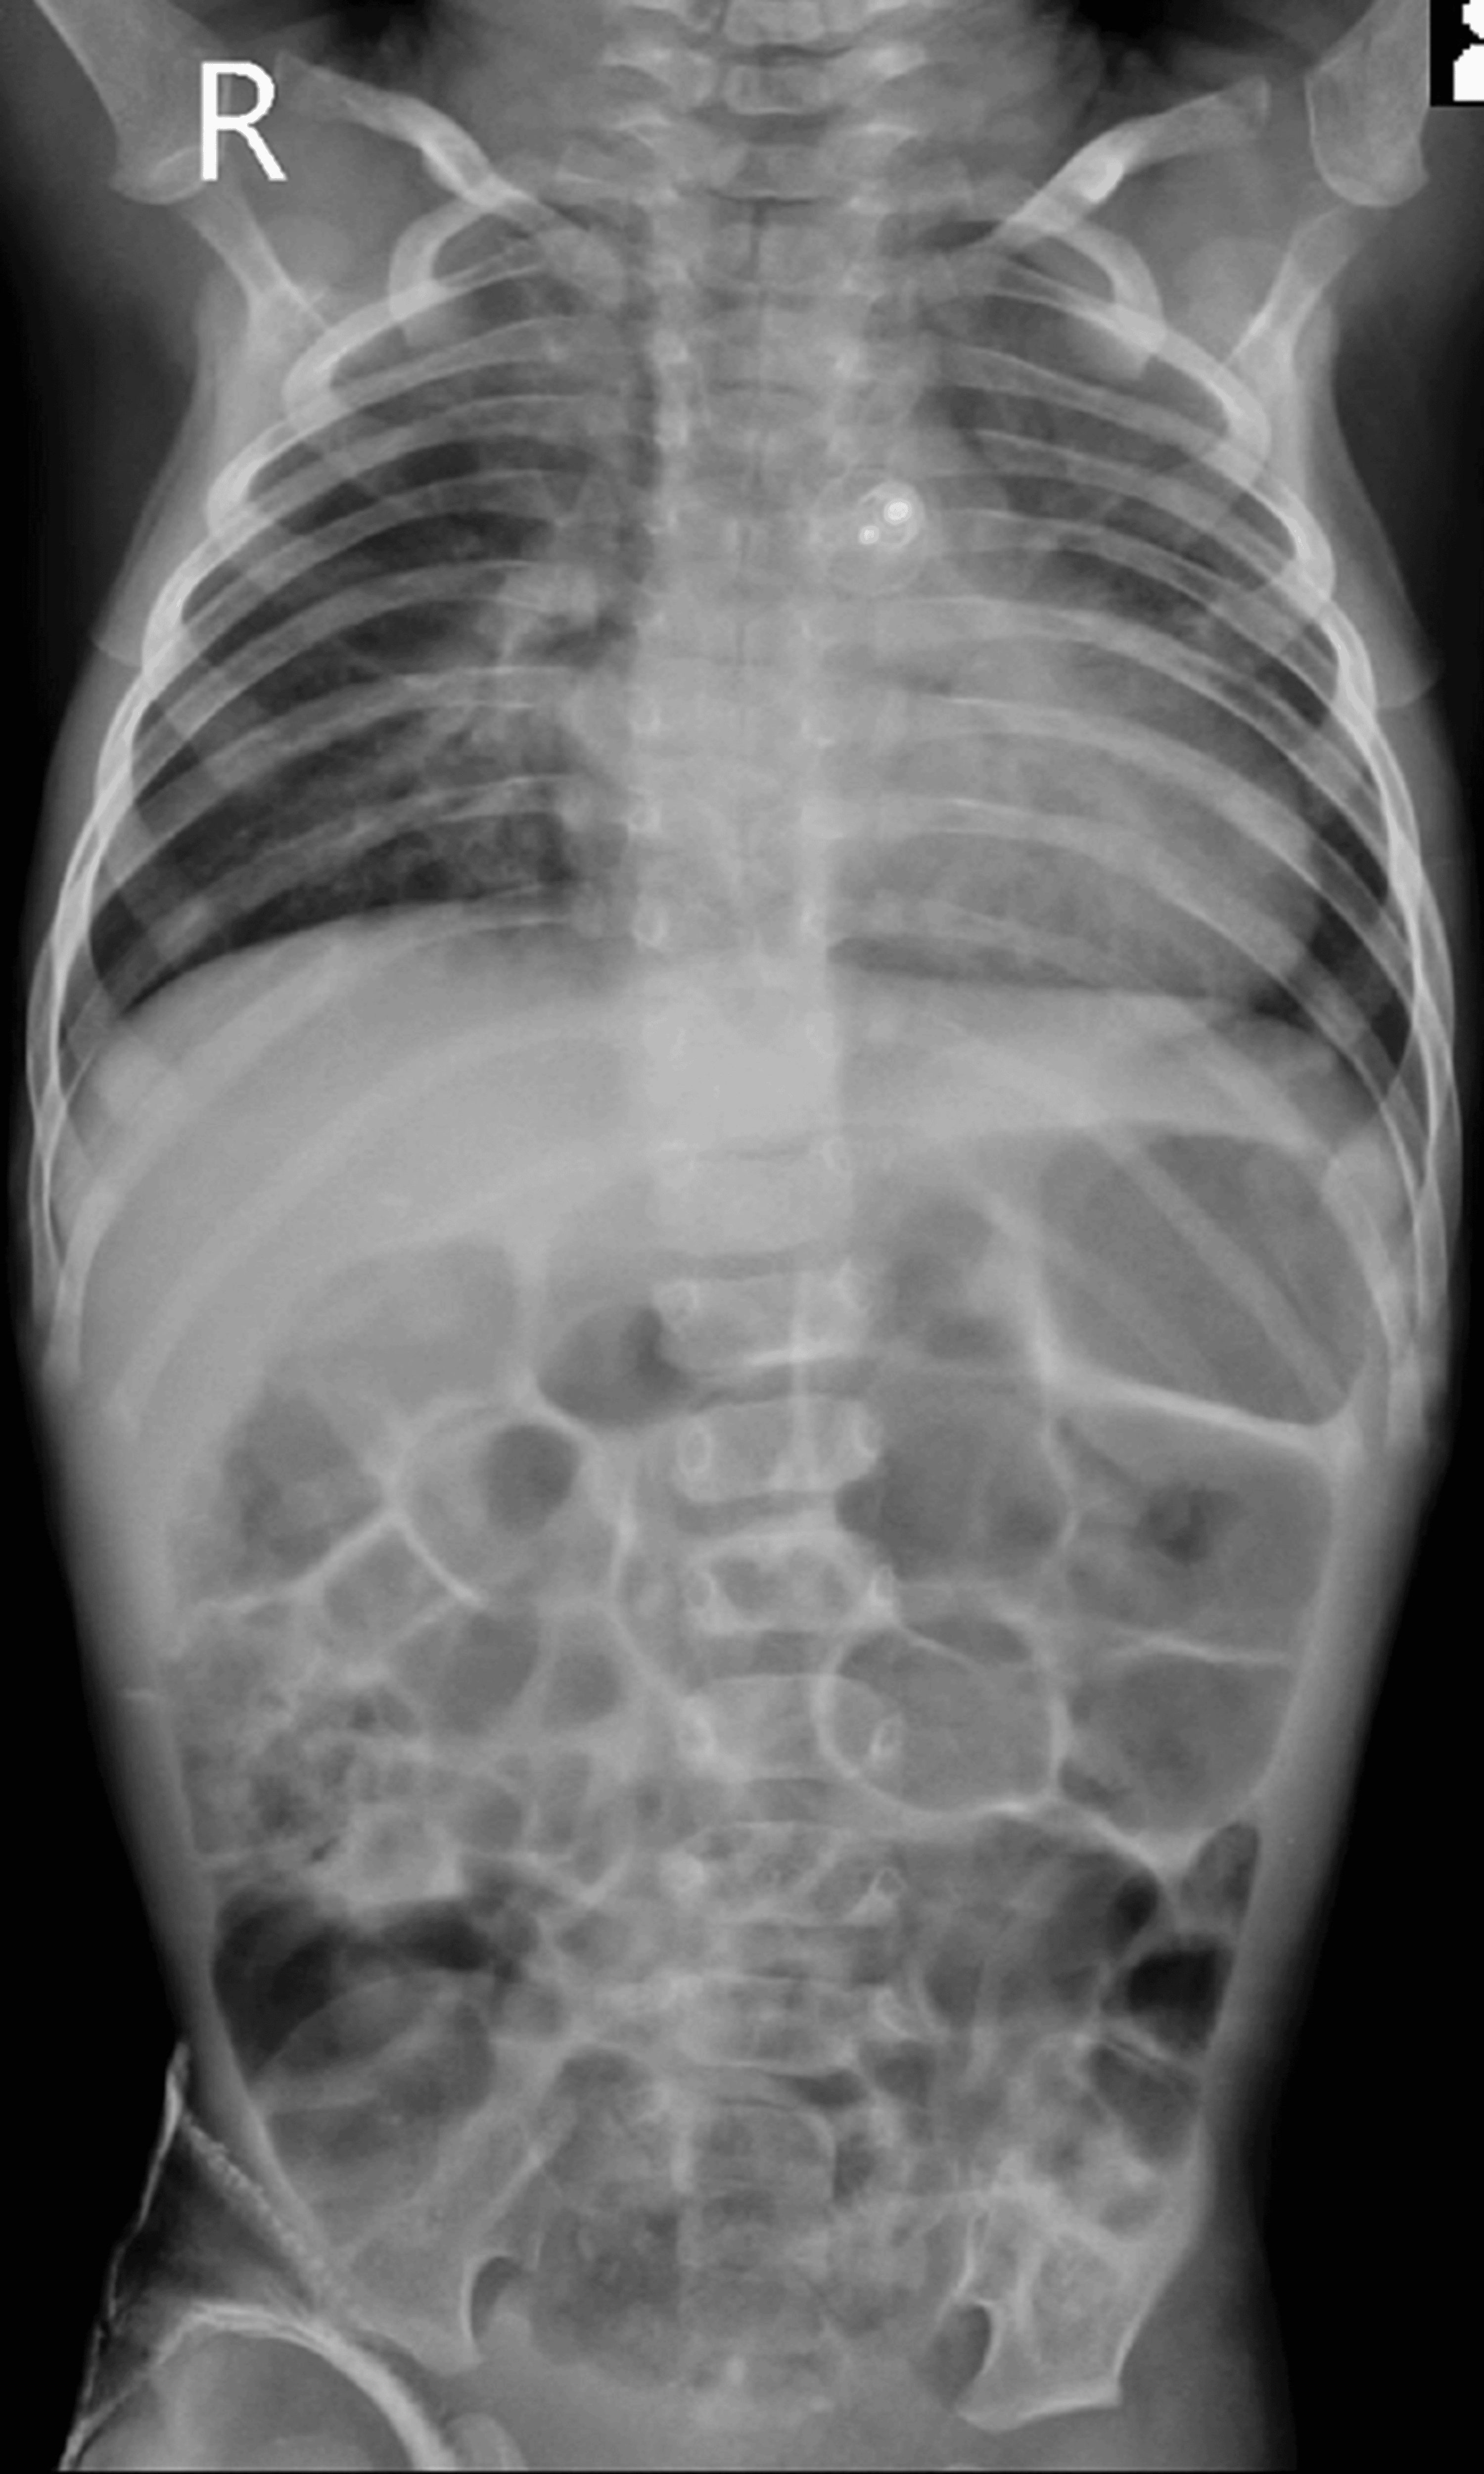

The patient was weaned off the ventilator and extubated the next day successfully, subsequently shifted to the pediatric intensive care unit (PICU), and handed over to a pediatric resident for further management. The patient received a unit of packed red cell transfusion in the PICU postoperatively. Follow-up chest radiography showed bilaterally clear lung fields with the PDA Amplatzer device (Abbott, Green Oaks, IL) in situ. He improved symptomatically and was discharged. The patient is doing well at home as per the last follow-up (Figure 3).